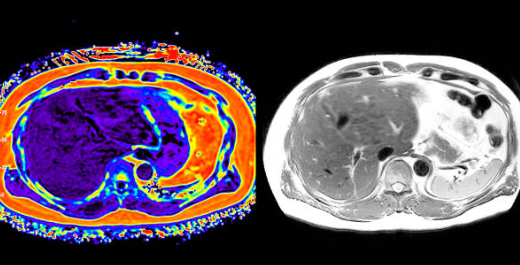

MRI와 MRA는 모두 자기공명영상 기술을 이용한 검사법이지만, 촬영 목적과 확인하는 부위에 차이가 있습니다. 이번 글에서 MRI와 MRA의 차이점, 검사 방법, 활용 질환, 장단점을 상세히 정리했습니다.

- 정의: Magnetic Resonance Imaging(자기공명영상)의 약자로, 자기장을 이용해 인체의 단면을 영상으로 얻는 검사

- 목적: 뼈, 근육, 신경, 장기 등 인체 연부 조직의 구조적 이상 확인

- 주요 활용: 뇌종양, 뇌졸중, 척추 질환, 관절 손상, 종양·염증 진단